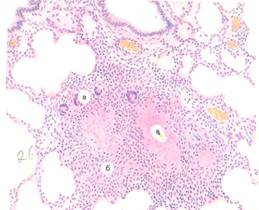

16) Миллиарный туберкулез легких

1. Название органа, ткани: Ткань легкого

2. Способ окраски: Гематоксилин и эозин, №26

3. Основные микроскопические изменения: В центре гранулемы - очаг казеозного некроза, окрашенный в светло-красный цвет. Вокруг очага много эпителиоидных клеток, снаружи расположена группа из клеток, состоящая из лимфоцитов и макрофагов, внутри которых встречаются многоядерные клетки Пирогова-Лангханса. По периферии встречаются Т-лимфоциты, макрофаги, плазмоциты, а так же немногочисленные капилляры.

а) Очаг казеозного некроза;

б) Лимфогистоцитарный очаг;

в) Гигантские многоядерные клетки Пирогова-Лангханса. По периферии гранулем скопления лимфоидных клеток.

4. Вид патологического процесса: Продуктивное гранулематозное воспаление (специфическое). При туберкулезе легочной формы.

5. Заключение: Туберкулезные гранулемы в легком